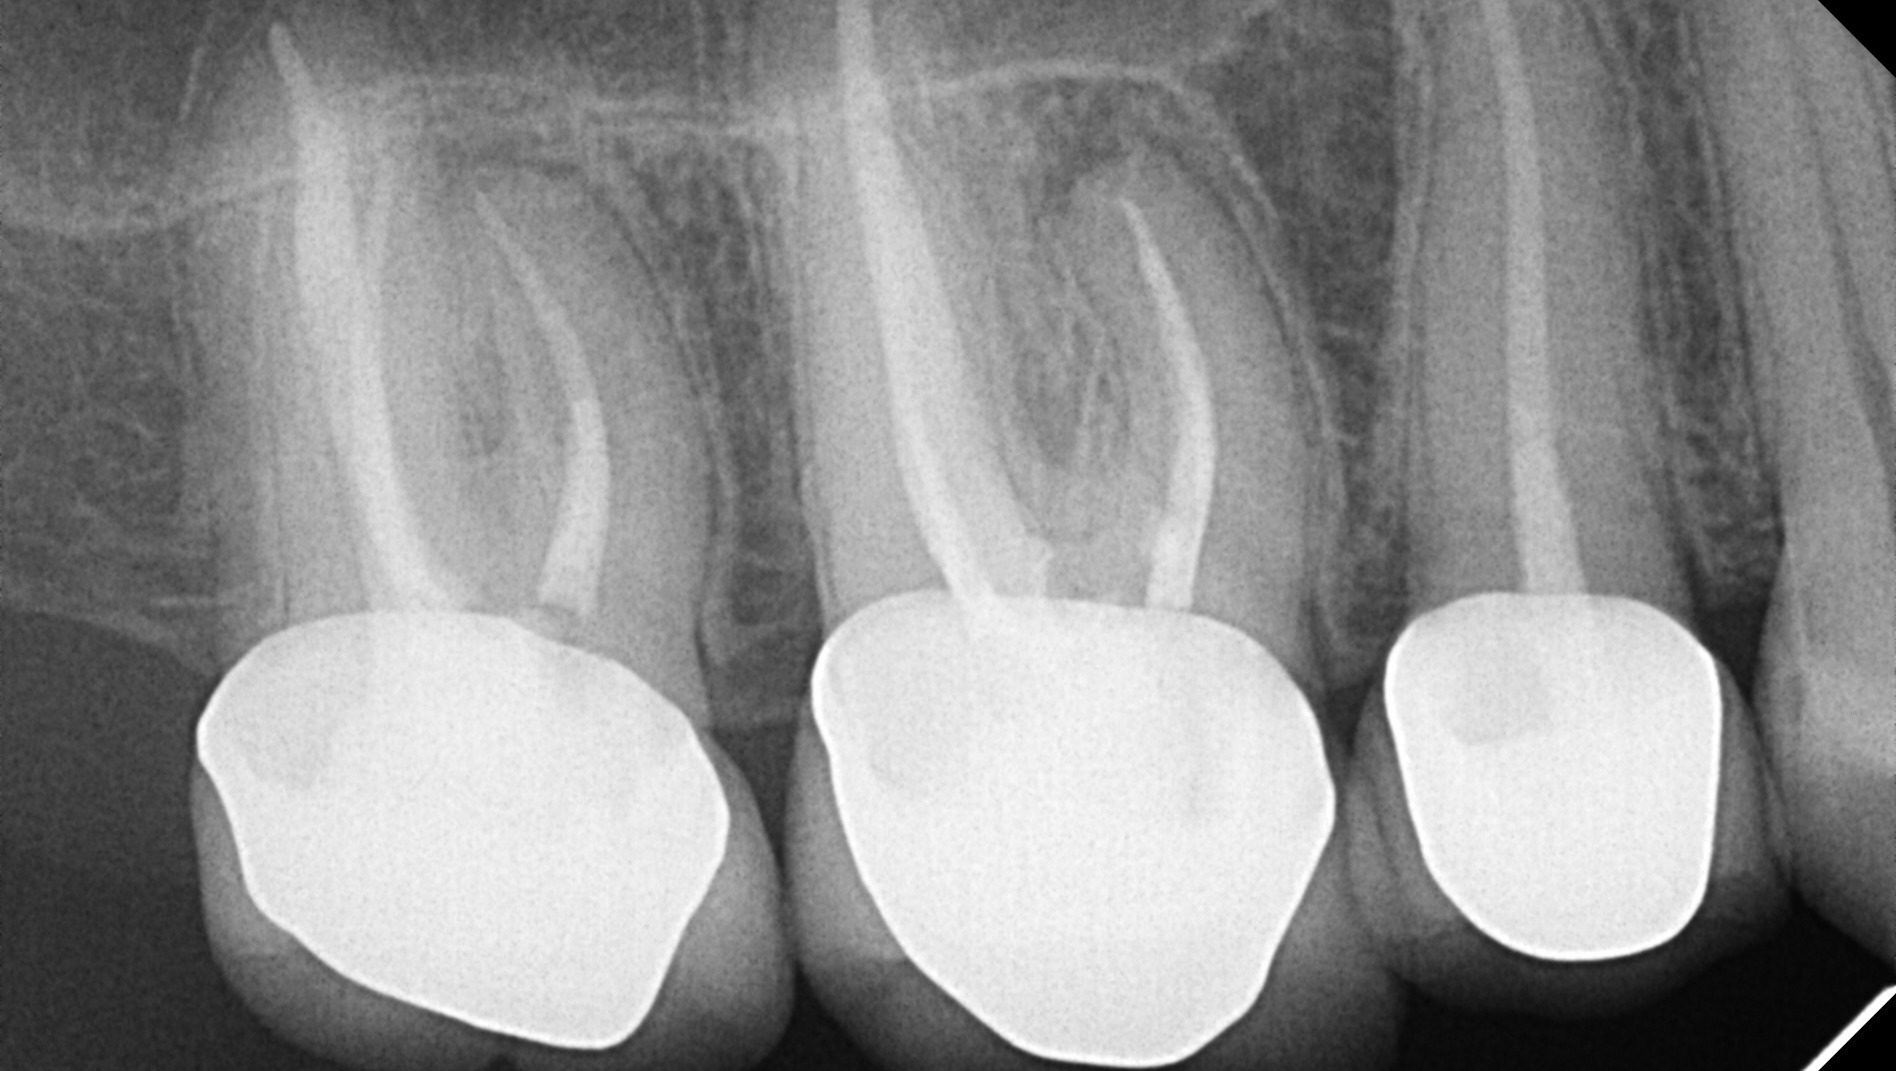

Those of you who know me know I’ve had a lot of dental procedures throughout my life. These procedures have ranged in severity—cavities turned root canals, root canals turned extractions, and so on. If you know me, you might know I am missing two molars on the right side of my bottom teeth; I haven’t chewed on that side in years. Almost all of my remaining molars have had root canals performed on them and have crowns.

To my incredible dismay, as of last month (January), I received a new diagnosis, and a new bill. I have two upper right molars that have root canals that have seemingly failed. They require what is called a retreatment—as the name aptly suggests, they re-treat the tooth, essentially performing another root canal to clean out the present infection. (This also means those glittering porcelain crowns I paid for by myself however many years ago will need to be replaced with new, equally as expensive crowns). I should note: these kinds of dental procedures, especially those in the upper region, are an urgent matter, as the infection is liable to spread if left untreated.